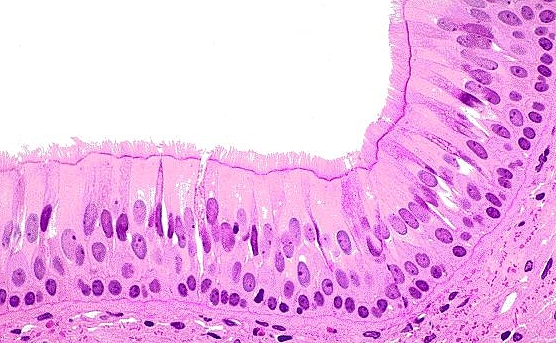

Microanatomy of the Lung

• Airway lining

• pseudostratified ciliated columnar cells extend to the bronchioles

• mucus secretions are swept out of the lungs toward the mouth by ciliated cells

• simple ciliated columnar epithelium extends to the terminal bronchioles

• ciliated cuboidal cells extend to the respiratory bronchioles

• alveolar sac are composed of pneumocytes

• goblet cells extend to the larger bronchioles but stop before the terminal bronchioles

• Type I pneumocytes

• 97% of alveolar surfaces

• line the alveoli

• squamous

• thin for optimal gas diffusion

• form blood-gas barrier with pulmonary capillary endothelial cells

• Type II pneumocytes

• 3% of alveolar surfaces

• secrete pulmonary surfactant within lamellar bodies

• dipalmitoyl phosphatidylcholine

• lowers the alveolar surface tension

• cuboidal and clustered

• serve as precursors to type I cells and other type II cells

• proliferate during lung damage

• Club (Clara) cells

• nonciliated

• columnar with secretory granules

• secrete component of surfactant

• degrade toxins

• act as reserve cells